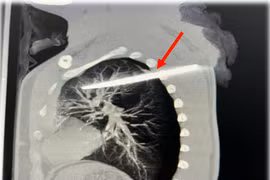

Cứu bệnh nhân 29 tuổi bị dao xuyên thấu lưng, cắm sâu trong phổi

Vết thương thấu ngực kèm dị vật luôn đe dọa khẩn cấp tính mạng người bệnh nên cần biết cách xử trí vết thương có dị vật để tăng cơ hội sống sót và giảm thiểu biến chứng cho bệnh nhân.